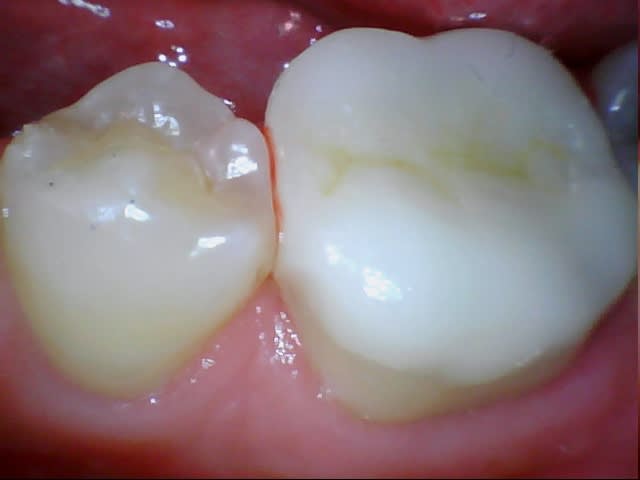

Je me suis lancé, on va voir ce que ça va donner la semaine prochaine. On mutile un peu moins c'est vrai, surtout qu'avec une prépa de dépouille pour une couronne on dézingue de fait beaucoup plus dans la partie occlusale.

J'ai tout recouvert en occlusal avec congé large.

Mis-à-part que les photos sont celles de ma cam (Chinese inside) qu'est-ce que j'aurais du faire ou ne pas faire ?

J'ai un peu peur pour l'esthétique du joint (e-max programmée) quels compos pour le collage vous semblent les plus indiqués puisque là faut pas compter sur une activation photo ?

Et d'ailleurs dans le cas d'un onlay uniquement occlusal sans boîte proximale faut-il compter sur une photo-polymérisation car ça ressemble un peu à une facette ?